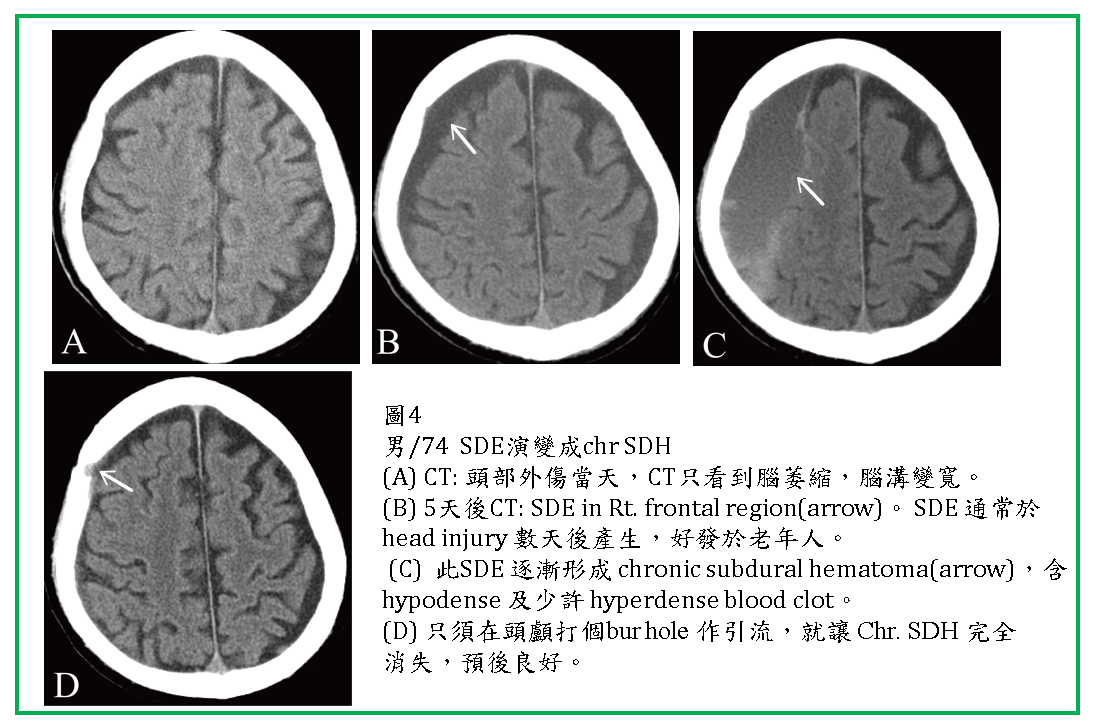

SDE通常位於大腦額頂葉外(圖1,2,3,4) ,有時也會在後顱窩,小腦天幕(tentorium)邊,及大腦鐮(falx)邊(圖3)。

SDE可能會再出血,形成SDE混合SDH(圖2) ,或逐漸形成 chronic subdural hematoma (CSDH) (圖4) .